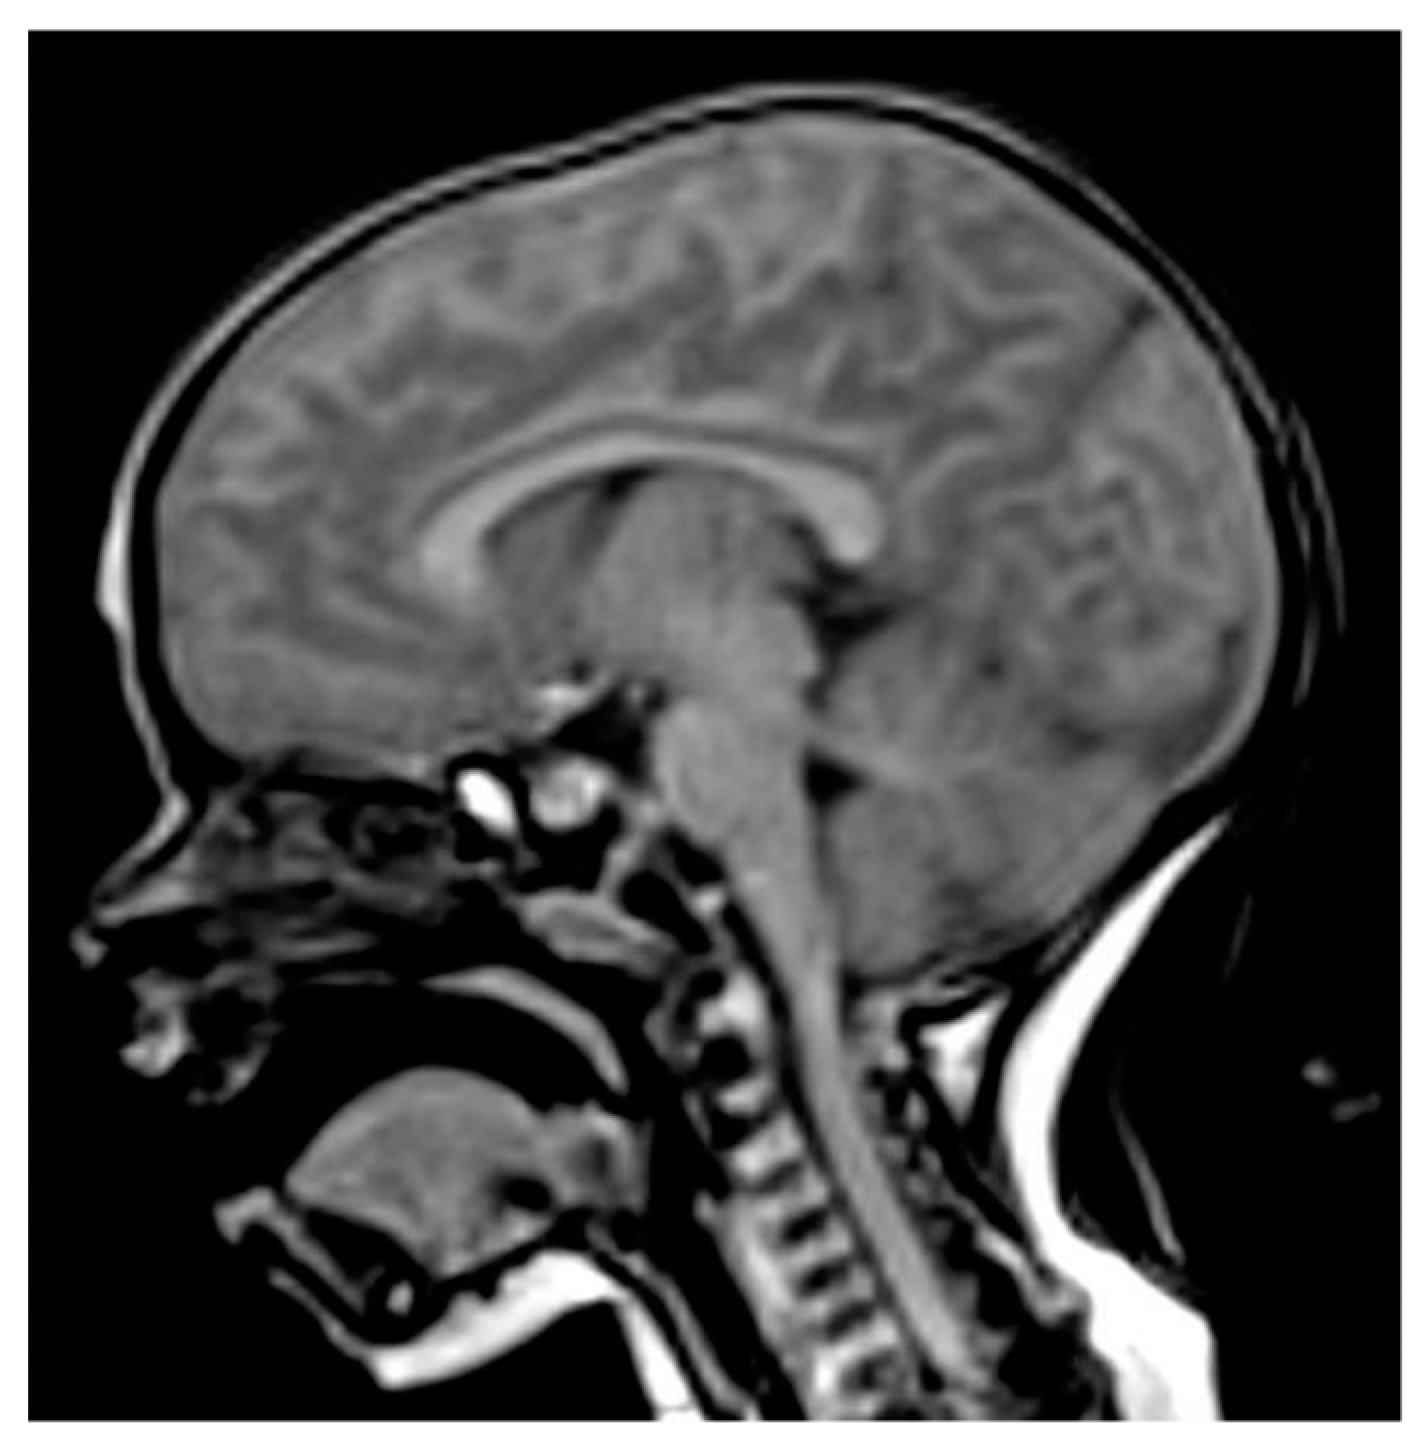

Pituitary magnetic resonance imaging (MRI) showed a T1 hyper-intense enlarged anterior pituitary (height 9 mm), symmetrical region with a patchy signal and low enhancement after contrast agent (gadolinium) injection, with no abnormalities in the pituitary stalk or the optic chiasm, and a normal posterior pituitary bright spot (Figure 1). Brain MRI was performed using a 3 Tesla magnet (Samsung, Seregno [MB], Italy). Sequences were acquired according to multiple planes and a thin layer on the diencephalon-pituitary region. The sequences were obtained before and after the intravenous administration of paramagnetic contrast medium (Dotarem 0.5 mmol/mL, tot 2.6 mL) with suppression of the adipose tissue signal.

Figure 1. Sagittal pituitary MRI image showing hyper-intense enlarged anterior pituitary (T1-weighted sequence).

All patients with PIT1 mutations and most patients with PROP1 mutations have either small or normal-sized anterior pituitary glands, but some patients carrying PROP1 mutations can present normal-sized or hypoplastic or even enlarged pituitary glands. Several patients with PROP1 mutations and pituitary enlargement are usually observed in early childhood, which is followed by pituitary hypoplasia [14]. The 301,302delAG mutation is the most frequent mutation and most patients with pituitary enlargement have been shown to harbor the 301–302delAG mutation. However, 150delA, Q83X, and R73C mutations have also been described as associated with pituitary enlargement. Usually, pituitary enlargement is followed by a waxing and waning size of the pituitary mass with hypoplastic pituitary at the end. In addition, the same mutation in siblings can occur with different pituitary morphologies [14]. Our case underlines the importance of MRI imaging in the diagnosis of children with hypopituitarism [6]. Differences in MRI pituitary gland morphology can suggest different GHD etiologies and prognoses. In our patient, the finding of an enlarged pituitary in a non-syndromic infant with two pituitary hormone deficiencies suggested a PROP 1 defect. Pituitary enlargement is sometimes dramatic but has a benign course and is followed by degeneration and regression [12]. Under such conditions, genetic testing offers an important tool for making therapeutic decisions in patients with pituitary mass and is indispensable in avoiding unnecessary neurosurgery [13].